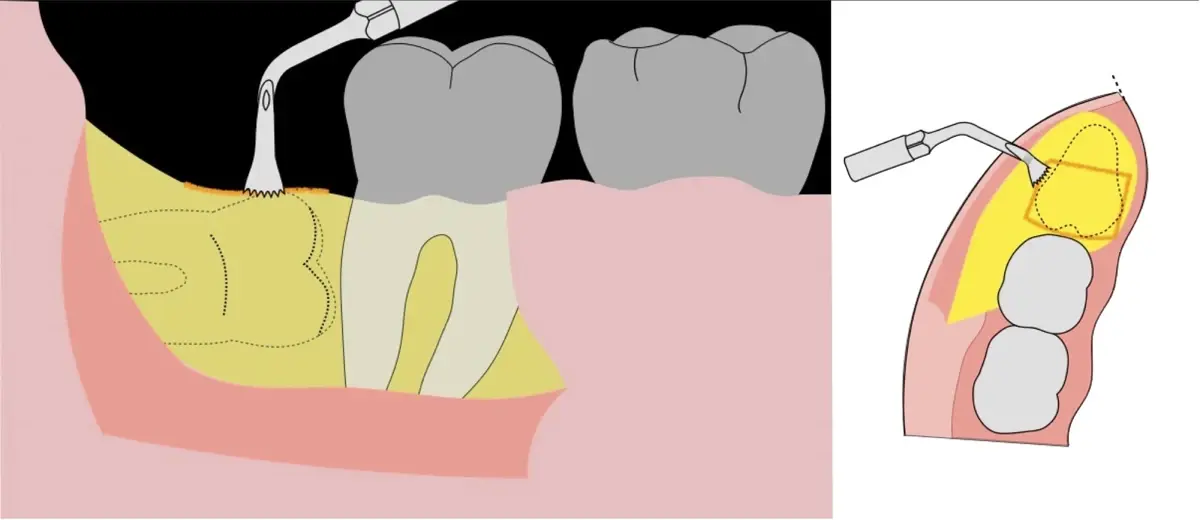

En contraste, el instrumento piezoeléctrico utiliza un corte micrométrico que retira un área de superficie mínima de hueso, y reduce el riesgo de termonecrosis marginal en comparación con las fresas rotatorias convencionales.9 Los micromovimientos mejoran la precisión en el corte y el control táctil, y eliminan las macrovibraciones que se producen con los instrumentos rotatorios.10 Su frecuencia de oscilación es la amplitud de 60-200 μm horizontalmente y de 20-60 μm en sentido vertical, lo que es muy inferior en comparación con las micro sierras oscilantes; por lo tanto, proporciona cortes de osteotomía precisos y seguros. Adicionalmente, posee vibraciones ultrasónicas que descomponen el líquido de irrigación en partículas muy pequeñas (fenómeno de cavitación, que produce un efecto hemostático y así reduce la pérdida de sangre), lo que proporciona una visión clara y sin obstáculos del campo quirúrgico11,12.

Jian Q. et al13 indicaron que, aunque los pacientes sometidos a piezocirugía experimentaron un tiempo de cirugía más prolongado, tuvieron menos inflamación postoperatoria, lo que indica que la piezocirugía es una técnica alternativa prometedora para la exodoncia de terceros molares impactados. Mientras que Rullo et al14 asocian las intervenciones más largas con más dolor, especialmente con la acción de corte micrométrico más lenta del dispositivo piezoeléctrico. Debe considerarse que el dolor después de la extracción del tercer molar también depende de otros factores asociados, como la extensión del levantamiento del colgajo, el tabaquismo, la higiene bucal, la edad, la ansiedad y la historia de pericoronitis.